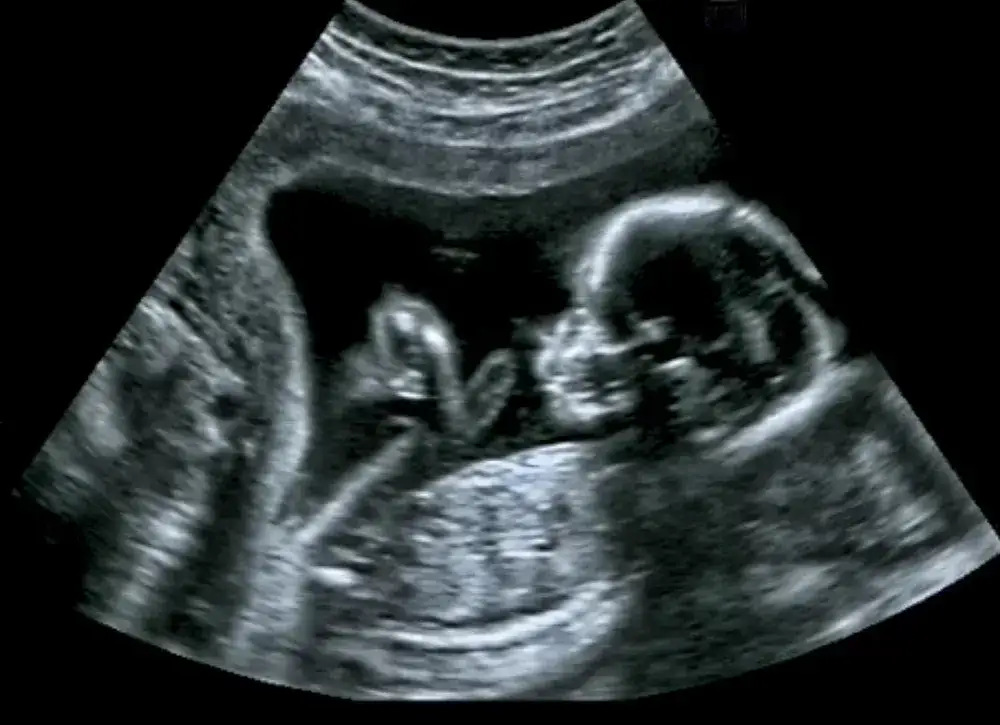

Badania połówkowe, znane również jako USG II trymestru, to kluczowe badanie obrazowe, które ma na celu ocenę rozwoju płodu oraz stanu zdrowia matki. Wykonywane jest zazwyczaj między 18. a 22. tygodniem ciąży, kiedy organy płodu są już na tyle rozwinięte, że można je dokładnie zbadać. Badanie to wykorzystuje ultrasonografię, która pozwala na uzyskanie obrazów wnętrza jamy brzusznej matki oraz rozwijającego się dziecka za pomocą fal ultradźwiękowych.

Podczas badania połówkowego lekarze przeprowadzają szeroką analizę anatomiczną płodu, aby ocenić jego rozwój i wykryć ewentualne wady wrodzone. Specjalista ocenia różne elementy, takie jak kończyny, głowa, kręgosłup, a także organy wewnętrzne, w tym serce, nerki i pęcherz moczowy. Analiza ta pozwala na dokładne zbadanie proporcji i symetrii ciała płodu, co jest kluczowe dla oceny jego zdrowia. Lekarz może także zmierzyć obwód głowy oraz długość kości, co jest istotne dla monitorowania tempa wzrostu płodu w porównaniu do norm.